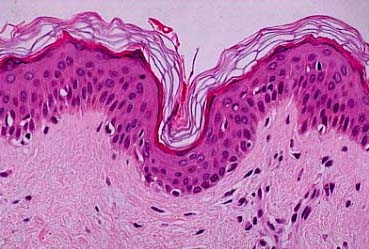

Normal Skin = مقطع في الجلد الطبيعي